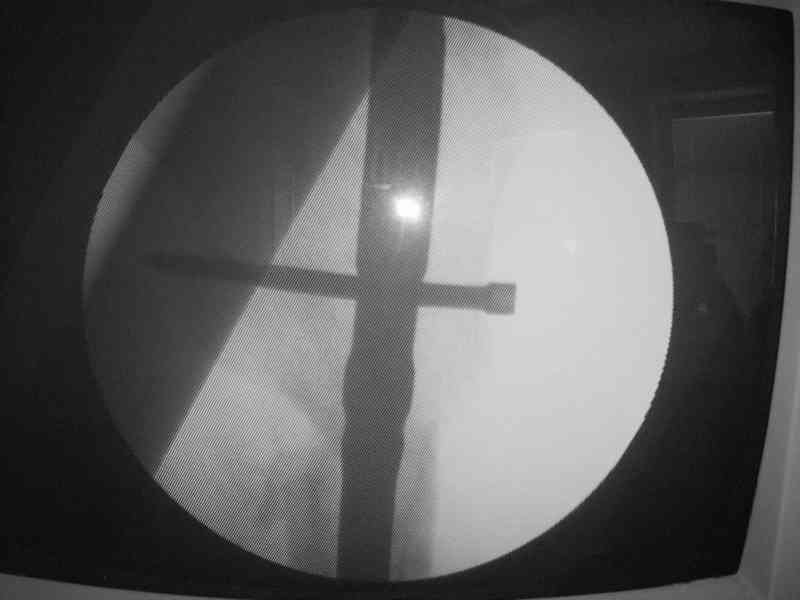

При межвертельных переломах с цефаломедуллярными гвоздями бывает, что проксимальый винт проходит или черед периферический отломок, или прямо над ним. И если остался диастаз, то этот винт при осевой нагрузке не дает сблизиться отломкам. Пример такого остеосинтеза в застарелом случае в приложении.

В качестве предупреждающей меры можно долотом разрушить латеральную стенку дистального отломка под винтом.